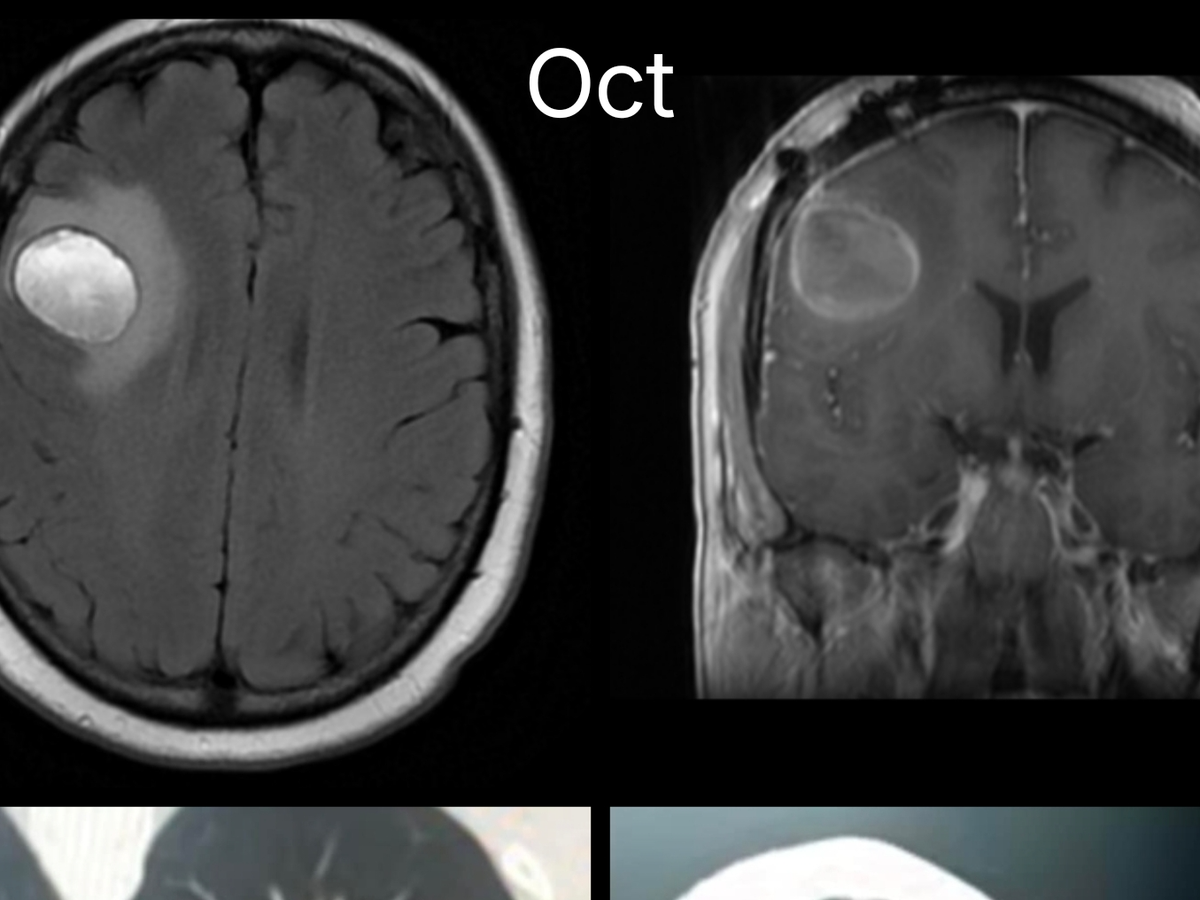

The first one was found incidentally this June, causing severe neurological symptoms, alongside the mass in her lungs also pictured. It turned out to be stage 4 metastatic melanoma. The 4 cm tumor was successfully removed, and she regained some function back in her left side. She has undergone gamma knife treatments and immunotherapy, traveling back and forth to San Francisco, Sacramento, Lower Lake, etc., to treat the 2-3 other small tumors in her brain, sticking it out even though the treatments wear on her. She was doing well....

A few weeks ago, she started having unrelenting headaches, blurry vision, and a feeling of fullness in her eyes... Close to the same area as large tumor #1, another tumor that was hardly noticeable before grew rapidly to almost the same size as the 4 cm tumor.